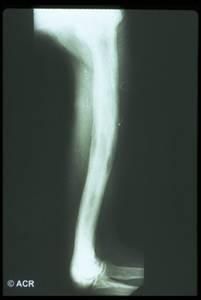

Anomalie scheletriche :

- tibia a sciabola

Comuni le fratture patologiche;

Reperti radiografici

Lisi ossea: riflette l'aumentata attività osteoclastica;

Sclerosi: riflette l'aumentata attività osteoblastica;

Aumento volumetrico dell'osso;

Lesioni litiche a "fiamma": riscontrabili a carico delle ossa lunghe;